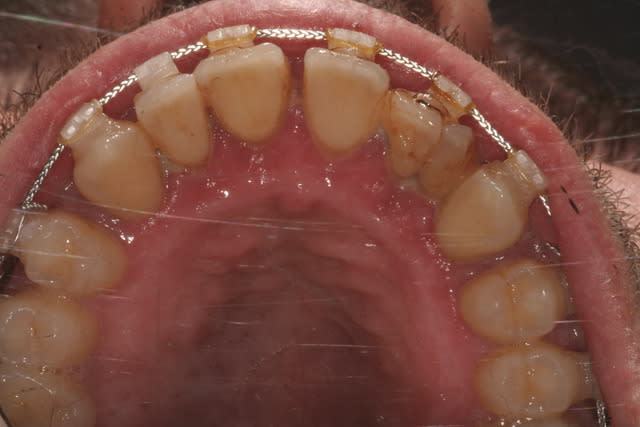

- Quid de la 22... Comment feriez vous ?

La 12 a un très mauvais pronostic :

- Plus de la moitié de la dent est en dehors de l'os.

- L'anatomie canalaire fait qu'un jour plus ou moins proche une infiltration aura lieu via le sillon médian de la gemination ou via le sillon palatin très profond.

- Cette anatomie fait qu'une tentative de séparation est vouée à l'échec.

Si tu veux lui rendre service : fais un compo vestibulaire et palatin très propre pour sceller les sillons de cette 12 géminée et améliorer l'esthétique, puis un stripping mésial et distal pour diminuer sa largeur.

Il faut gérer la parodontite (recessions visibles secteur 2, pertes osseuses sur la radio, gingivite...).